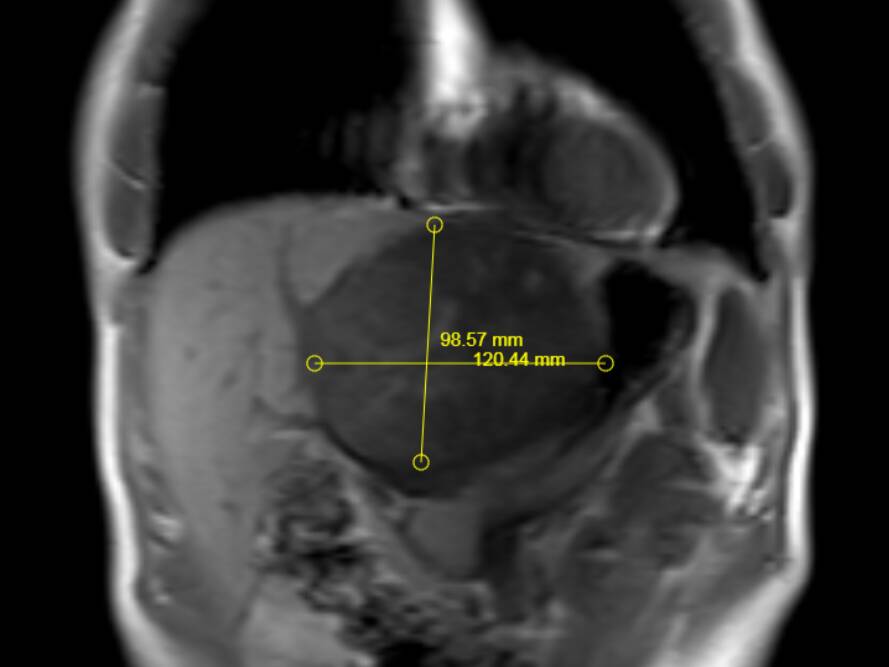

其中,成功为一名患者实施超大肝癌切除术,完整切除肿瘤大小达19cm×15cm,精准突破肝胆外科传统“手术禁区”,标志着普外二科在复杂肝胆肿瘤外科治疗领域迈上全新台阶。

此次切除的肿瘤体积巨大、血供丰富,与肝内重要血管、胆管粘连紧密,术中极易发生大出血、胆漏、肝功能衰竭等致命并发症。手术既要确保肿瘤完整根治、切缘干净,又要最大限度保留正常肝组织,难度与风险远超常规肝癌手术,对团队技术、经验与协作能力提出极高要求。

术前,科室联合影像、麻醉、重症监护、护理等多学科团队开展MDT会诊,全面评估肿瘤位置、大小、浸润范围及患者基础状况,精准规划切除路径与血管保护策略,反复推演手术流程,制定周密手术方案与应急预案,为手术成功筑牢坚实安全防线。

术中,手术团队在胡三元特聘专家与赵承乾科主任指导下,凭借精湛外科操作与丰富临床解剖经验,在高清手术视野下精细分离、逐层剥离、精准控切,妥善保护肝门部血管、胆管等关键结构,平稳完整剥离并切除巨大肿瘤,全程出血少、创伤可控,顺利完成高难度根治操作。